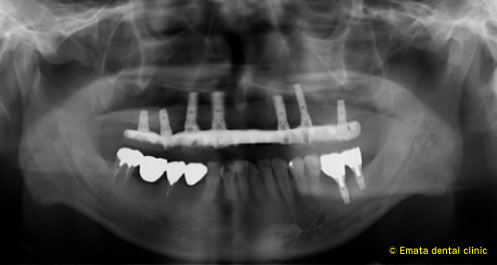

All-on-4は4本ではないかとおもいますが、骨の状態や対合歯が自分の歯なのでより確実性をもたせたいため5本で立ち上げ、2本はスリープさせました。

この症例のポイントは、ソケットリフト部位への即時負荷でしょう。アダプテーションテクニックにより40ニュートンの初期固定がえられました(専門的になってしまいましたね)。

麻酔専門医の先生が静脈内鎮静法を行っていますので患者さんは半分寝ているうちに手術が終わってしまいます。